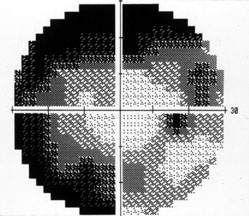

Humphrey 视野检查

• OD: 鼻侧视野缩窄(图 2)

• OS: 不能查

2